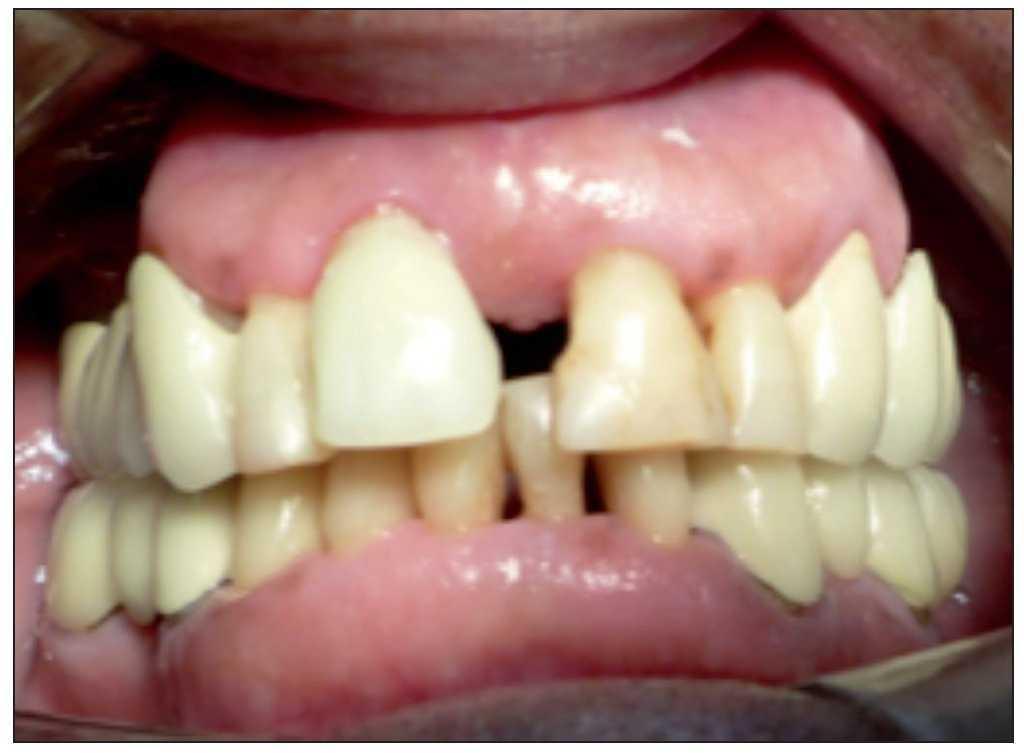

Figura 1. Visible discrepancia estética en posicion del margen gingival entre piezas 8 y 9.

Se seleccionaron 8 pacientes dentro del Programa de Especialización en Periodoncia e Implantología de la Universidad Mayor. Cada uno de estos pacientes (2 hombres y 6 mujeres, rango de edad 21-56 años) presentaba indicación de extracción de una pieza anterosuperior, asociada a una pérdida de tejidos duros y blandos, la cual generaba una alteración estética importante en relación con las piezas vecinas, asociada a una pérdida total de la tabla ósea vestibular.

Figura 8. Discrepancia severa en posición de margen gingival entre piezas 8 y 9.